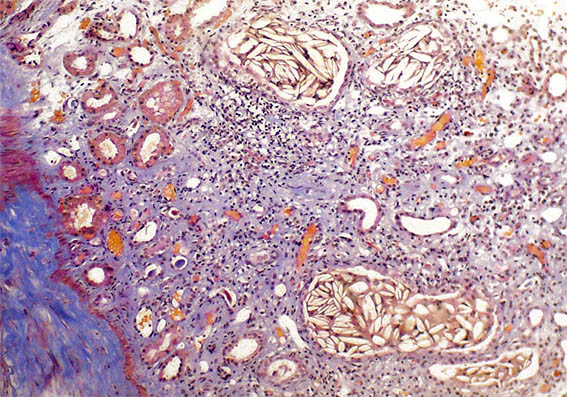

Figura 3.

H&E, X400. Zonas con marcada inflamación intersticial y daño tubular.

Figura 4. H&E, X100.